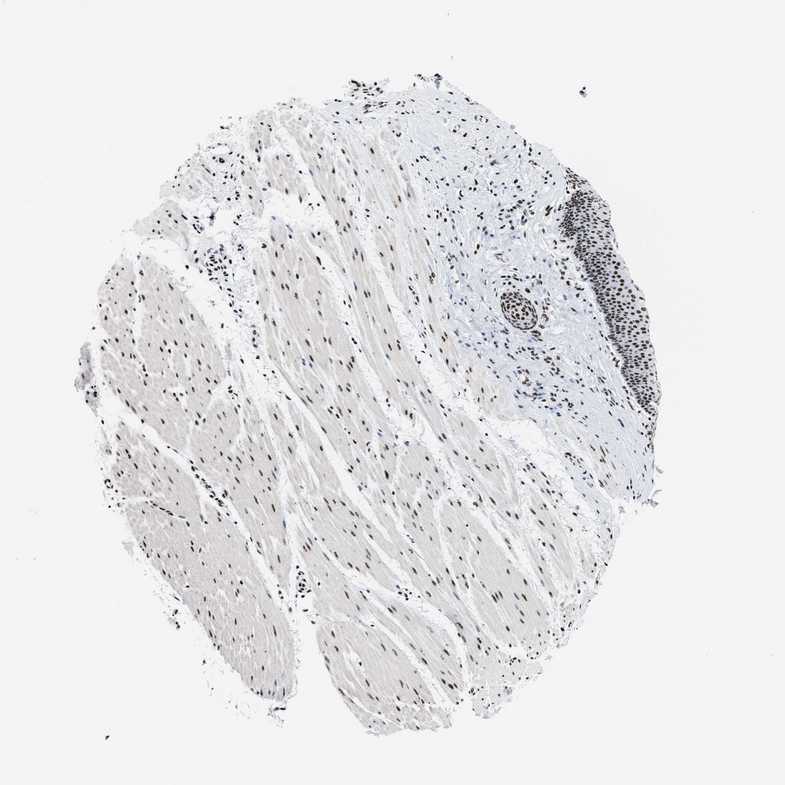

ESOPHAGUS - Antibody stainingi

Antibody staining in the annotated cell types in the current human tissue is reported as not detected, low, medium, or high, based on conventional immunohistochemistry profiling in selected tissues. This score is based on the combination of the staining intensity and fraction of stained cells.

Each image is clickable and will lead to virtual microscopy that enables deeper exploration of all samples and also displays staining intensity scores, fraction scores and subcellular localization as well as patient and tissue information for each sample.

Antibody HPA021213Antibody CAB004321

Squamous epithelial cells HighHigh